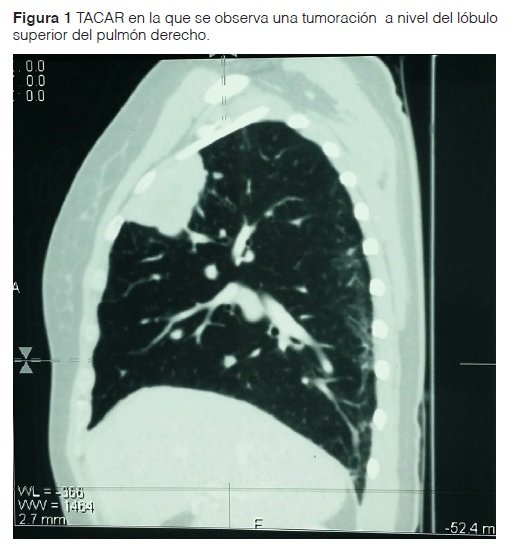

Paciente femenino de 45 años de edad conocida del servicio de clínica médica portadora de artritis reumatoidea de 9 años de evolución en tratamiento con Metotrexate 15 mg/día e Hidroxicloroquina 400 mg/día y prednisona según necesidad. Actualmente acude al servicio por presentar tos seca de 3 meses de evolución, continua, acompañada de disnea de moderada intensidad que se exacerba con los esfuerzos. Se le solicita TAC de tórax donde no se constatan hallazgos concluyentes por lo que se realiza TACAR con contraste donde se visualiza lesiones compatibles con linfangitis carcinomatosa y tumoración en pulmón derecho (Fig. 1), hígado y columna vertebral por lo cual se solicita biopsia.